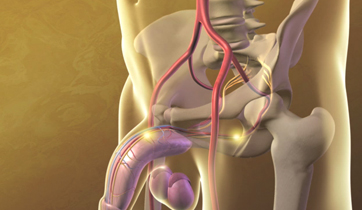

Erectile Dysfunction

Medtronic Corporation

This animationis intended to explain Erectile Dysfunction to physicians. It shows the vessels and nerves involved in blood flow obstruction to the penis, and the erectile tissue's failure to enlarge. The animation also suggests the benefits of clearing the obstruction by using stents.